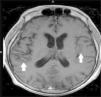

Magnetic resonance imaging (MRI) of the brain showed scattered areas of abnormal parenchymal signal intensity likely from tuberculous meningoencephalitis (Fig. 1). Computed tomography (CT) of the chest, abdomen and pelvis revealed necrotic mesenteric lymph nodes and splenomegaly.